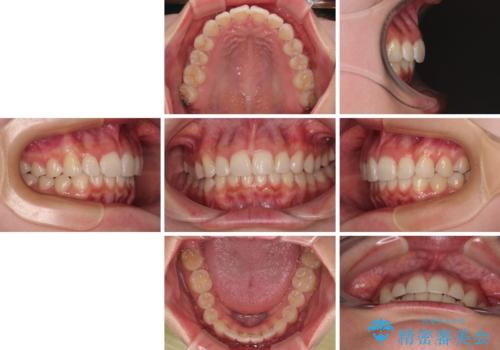

デコボコと咬み合わせを改善 インビザライン矯正治療

- 前歯のデコボコと突出感を気にして来院された患者様です。

極力目立たない装置を希望とのことで、インビザラインを用いて非抜歯で矯正治療を行うこととしました。

事前に親知らず2本を抜歯し、多少歯列を後方に移動できるように準備をした上で、なるべく歯と歯の間を削ることなくデコボコを解消できるように計画しました。

前歯の捻れを改善するとともに、口元が少しでも引っ込むように治療計画を立て、仕上げることができました。